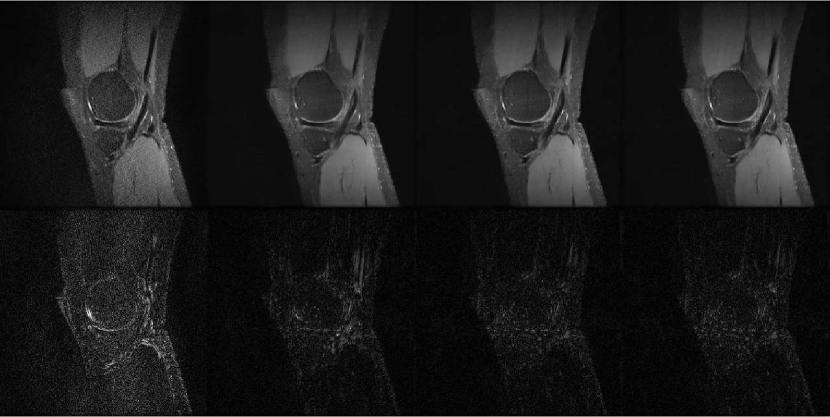

To determine the value of , we first test the our model with with 1 trial for each value, using the loss function stated in Eq. 3. We use the with the least MSE for the remaining experiments. The plot of the testing loss for different is in Fig. 3(a). To evaluate the performance of the RD-U-Net model, we compared the reconstruction results with GRAPPA [2] and U-Net [17]. Tab. 1 report the results for 5 different runs, and Fig. 5 illustrates sample visual results. For the zero-filled reconstruction, there exists a lot of aliasing artifacts (see Fig. 4(c)). Although GRAPPA removes the aliasing artifacts, the reconstructed image is still with a lot of noise (Fig.5(a)). The U-Net approach is better than GRAPPA, but the result is still lack of details (Fig. 5(b)). The proposed RD-U-Net provides a better reconstructed image with the presentation of residual dense block. In Fig.5(c), we can see that the result is sharper at the edges, and clearer for the details. The Fourier constraint is also useful for obtaining a better reconstruction, as shown in Fig. 3(b), adding the such regularization leads to lower MSE.

| (a) (b) (c) (d) |

![]() |